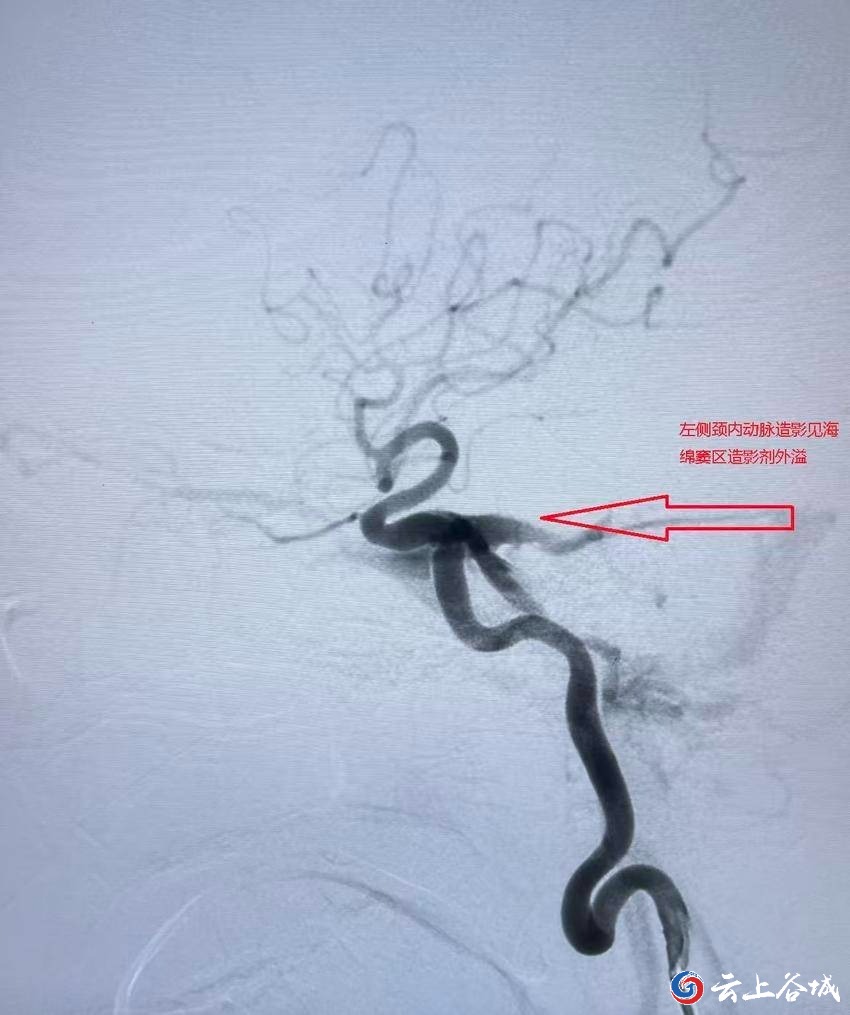

徐阿姨到谷城县人民医院就诊,谜底才终于揭开。医生们经过详细的脑血管检查,被确诊为“左侧颈内动脉海绵窦瘘”。

颈内动脉海绵窦瘘的诊断与治疗需要精准的脑血管评估。县人民医院神经外科团队为徐阿姨做了全脑血管造影检查,清晰显示动脉血直接流入海绵窦的异常通道,并明确瘘口的位置和大小。